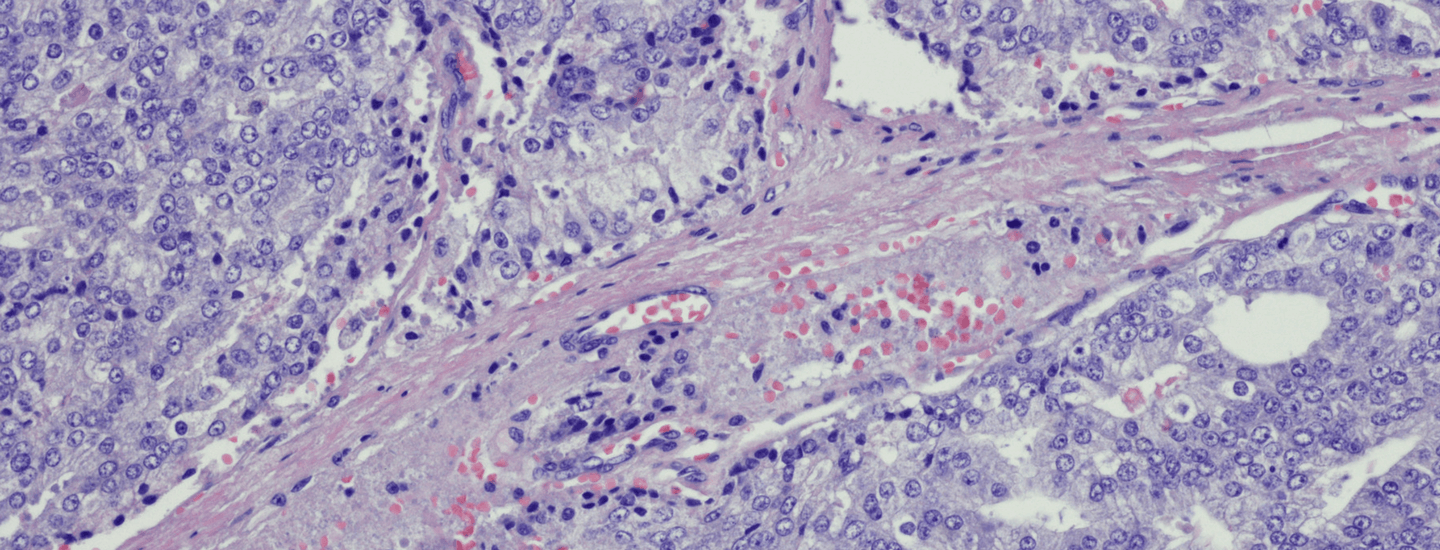

from shutterstock.com